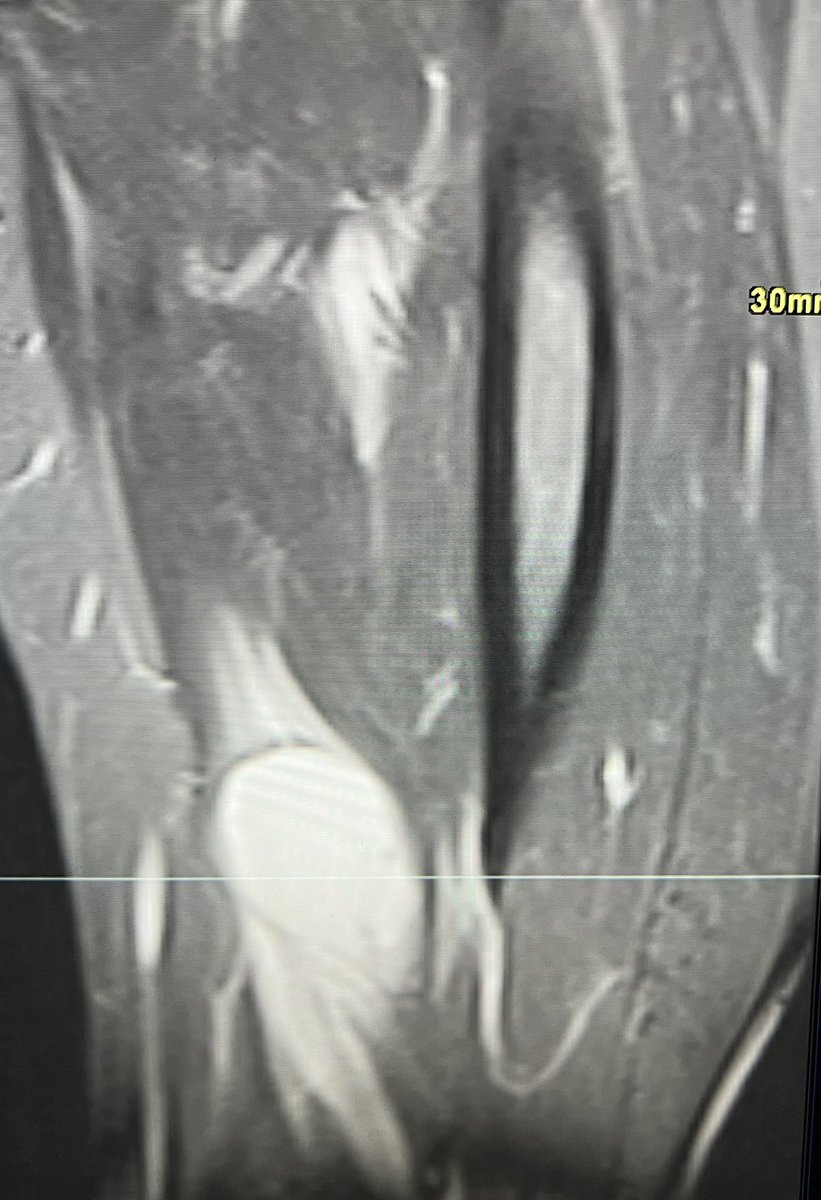

@mskteachingroom Intramuscular Myxoma - if multiple a/w fibrous dysplasia in Mazabraud syndrome